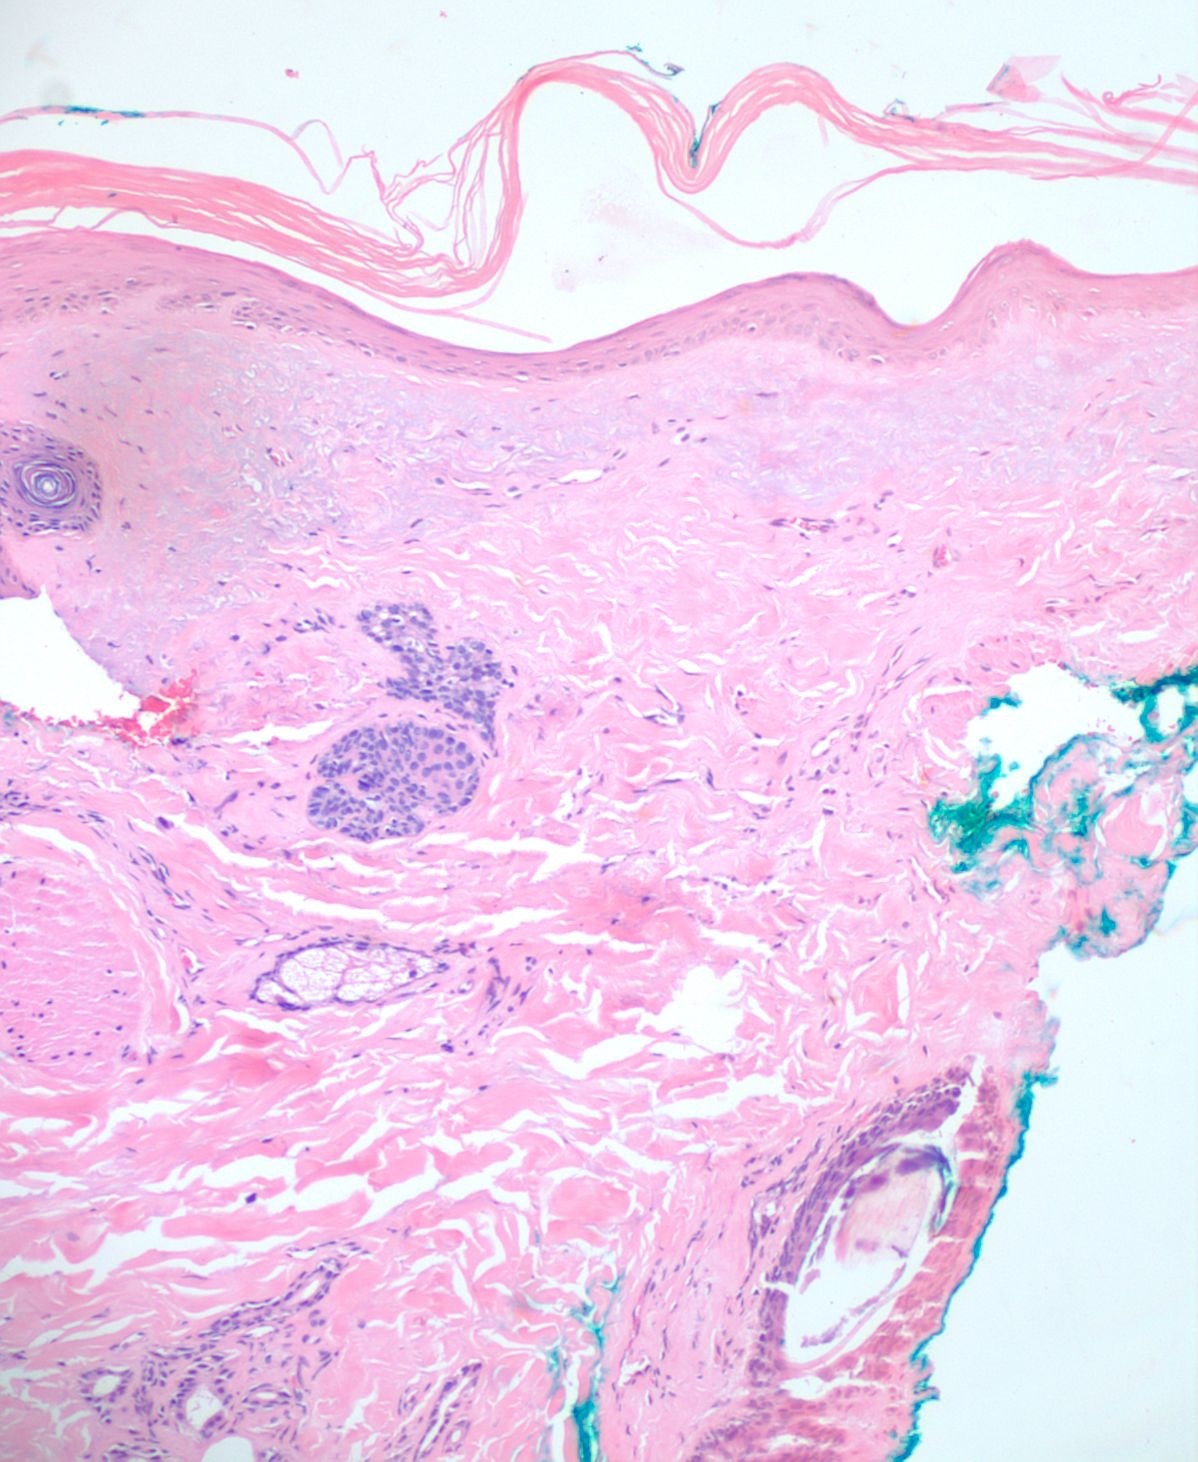

A 4mm. punch biopsy of the atrophic area on the left cheek was completed. Histology was consistent with late stage morphea, characterized by deep dermal sclerosis with thick, hyalinized collagen bundles (see Figure 2). Based on the clinical course and histologic findings, the patient was diagnosed with Parry Rhomberg syndrome, also known as PHA. The patient was referred to a rheumatologist and neurologist for further assessment of associated joint paint and muscle spasms of the jaw. A diagnosis of seronegative rheumatoid arthritis led to the addition of Celebrex for his joint pain. An MRI and EMG were recommended to rule out underlying musculoskeletal involvement. The patient elected to undergo systemic treatment with methotrexate, secondary to rapid advancement of the morphea and musculoskeletal symptoms. After one month of treatment, the hypopigmentation, jaw stiffness, and muscle spasms were subjectively improved.

Once a clinical diagnosis of PHA has been made, a multidisciplinary approach helps ensure that systemic manifestations are evaluated and treated appropriately. The diagnosis of PHA is primarily clinical. Still, biopsies are commonly performed for further diagnostic confirmation. Histopathologic analysis can reveal atrophy of the epidermis, dermis, and adnexal structures, and hypertrophy of collagenous fibers in the superficial dermis is characteristic (see Figure 2).2,4,5 As already stated, an MRI, ophthalmologic exam, and rheumatologic screening serology should be performed upon diagnosis. Photographical records from the time of diagnosis are recommended to follow disease progression and duration.4 Ultrasound tests can also be used to monitor disease activity and progression by measuring dermal thickness and echogenicity of affected areas. Increase in dermal blood flow can be seen on color doppler as a sign of active disease.4,14,15